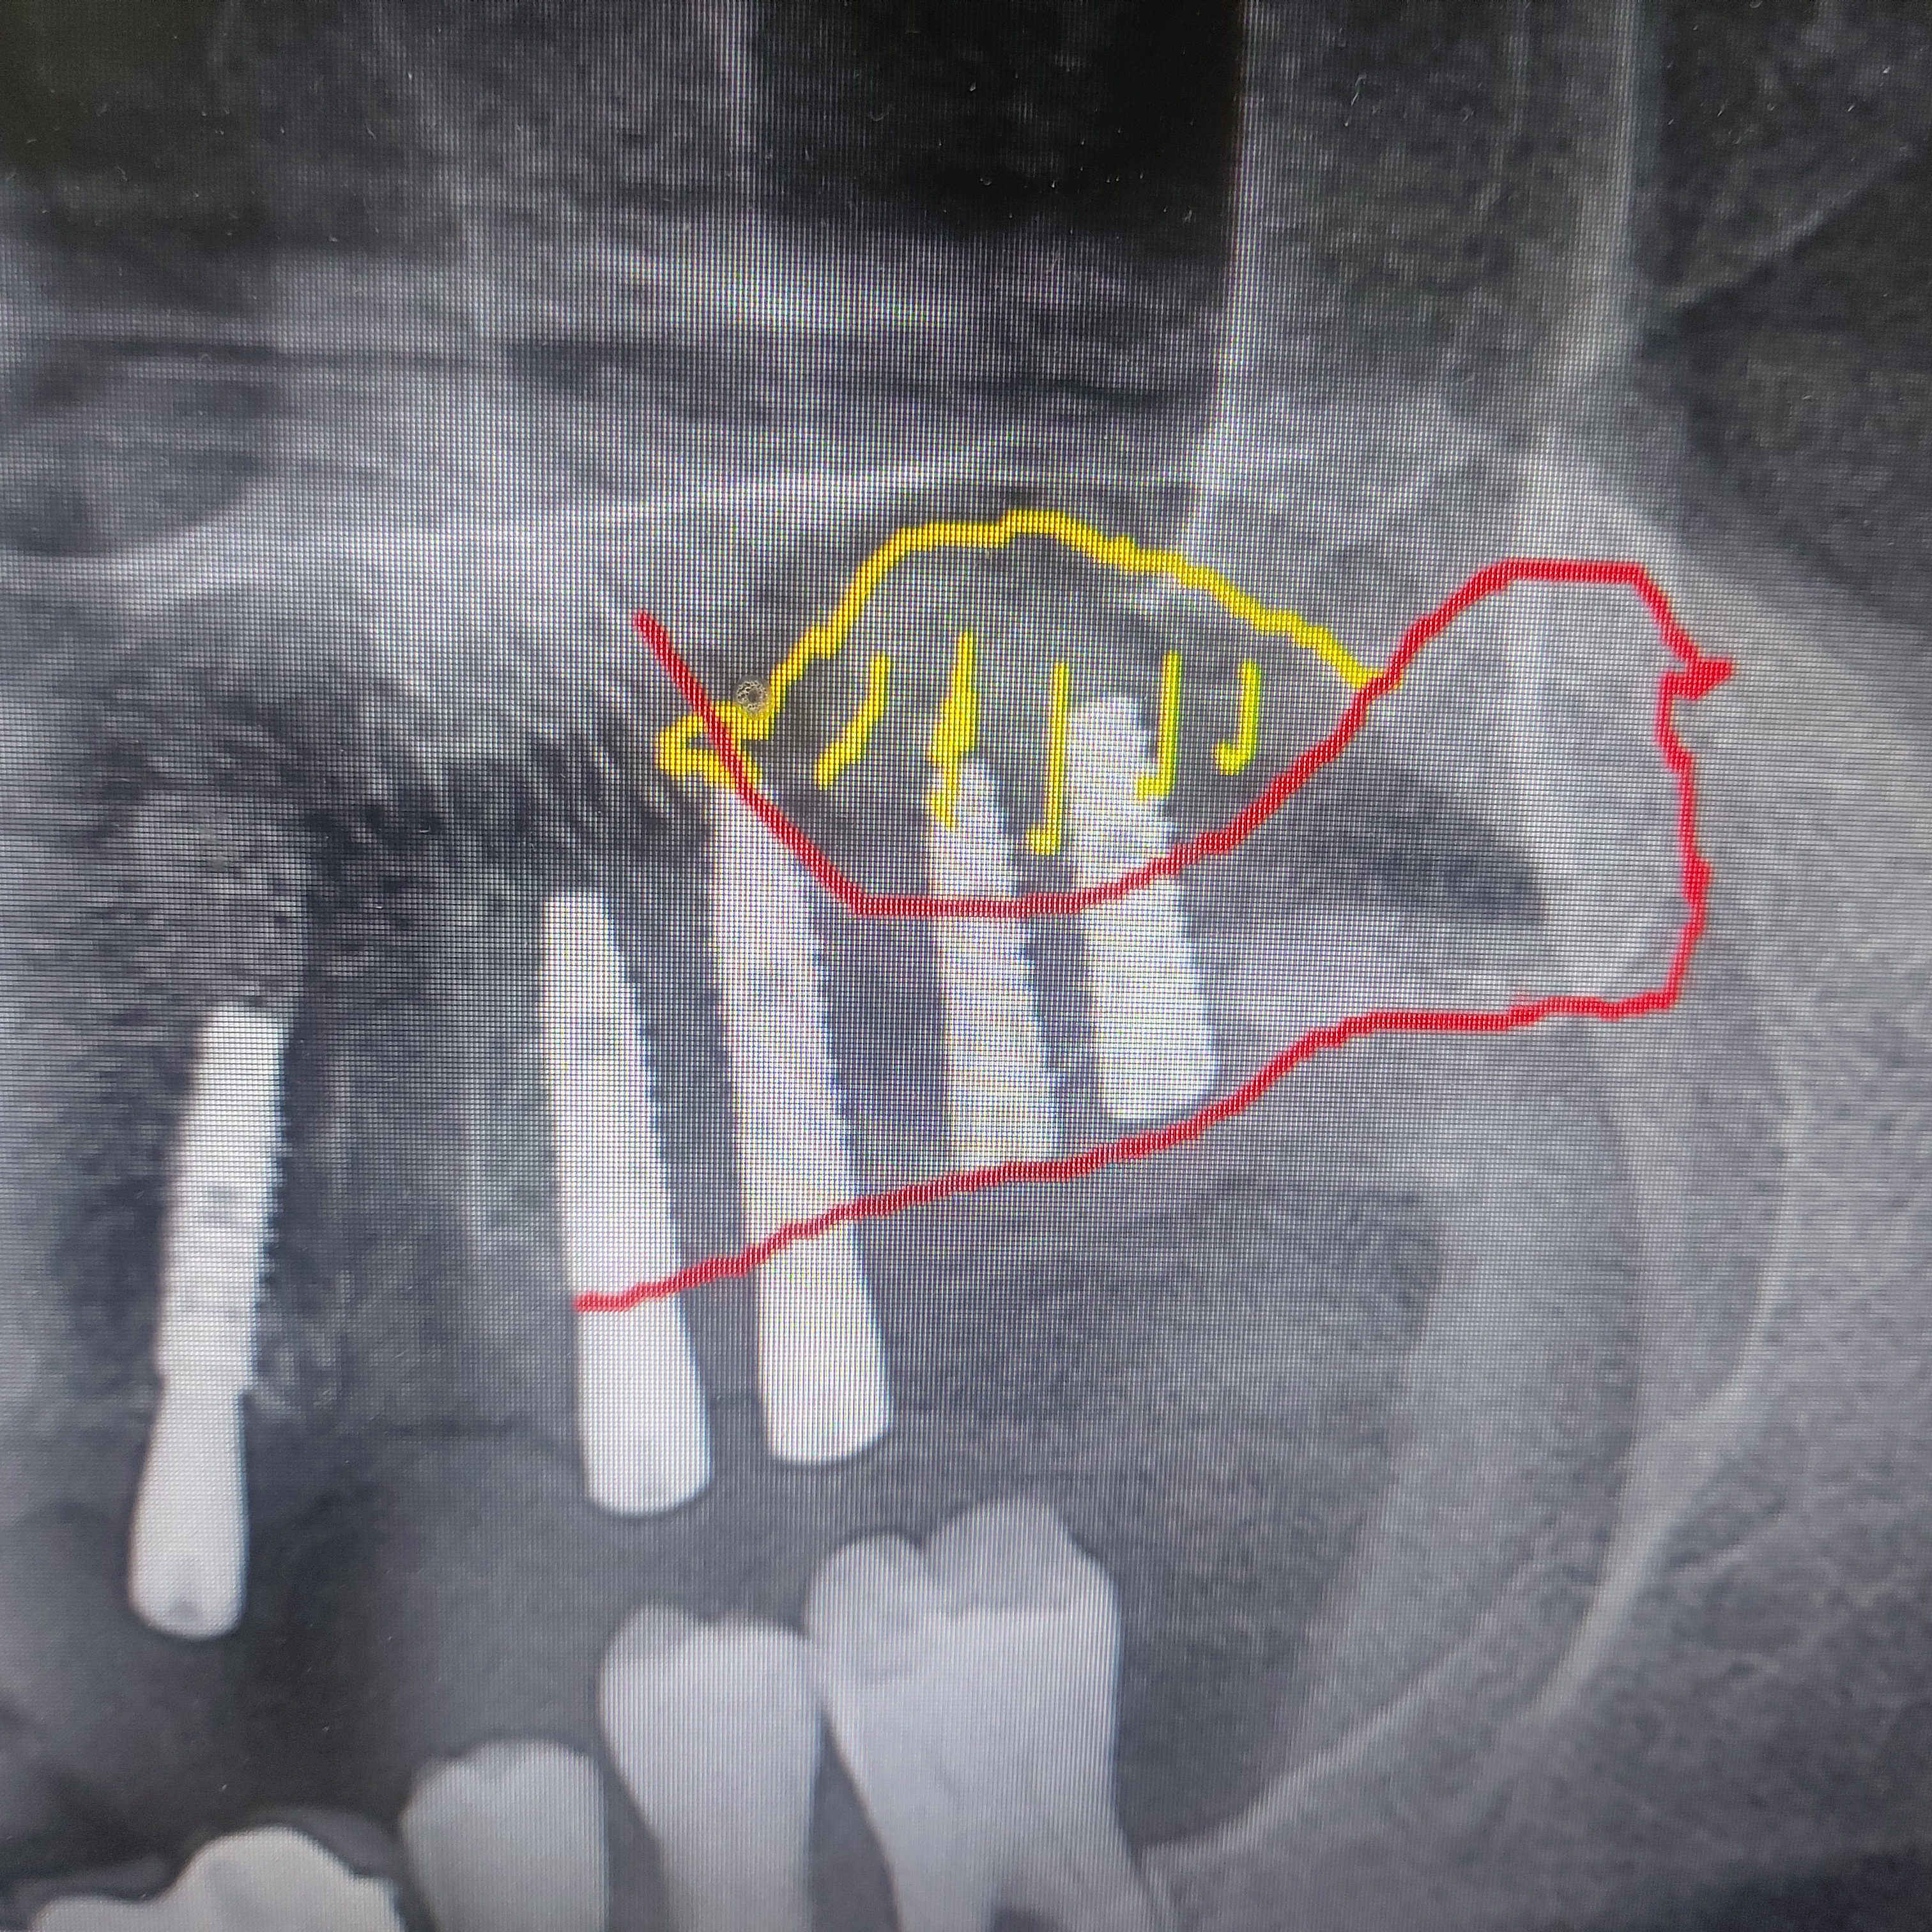

♤ 이 환자분의 양질의 튼튼한 임플란트를 위해서는 꼭 왼쪽 상방에 상악동 거상술이 시행되어야 한다는 사실이 떠올랐습니다.

그리고 좌측 상방은 상악동 거상술을 시행하였습니다.